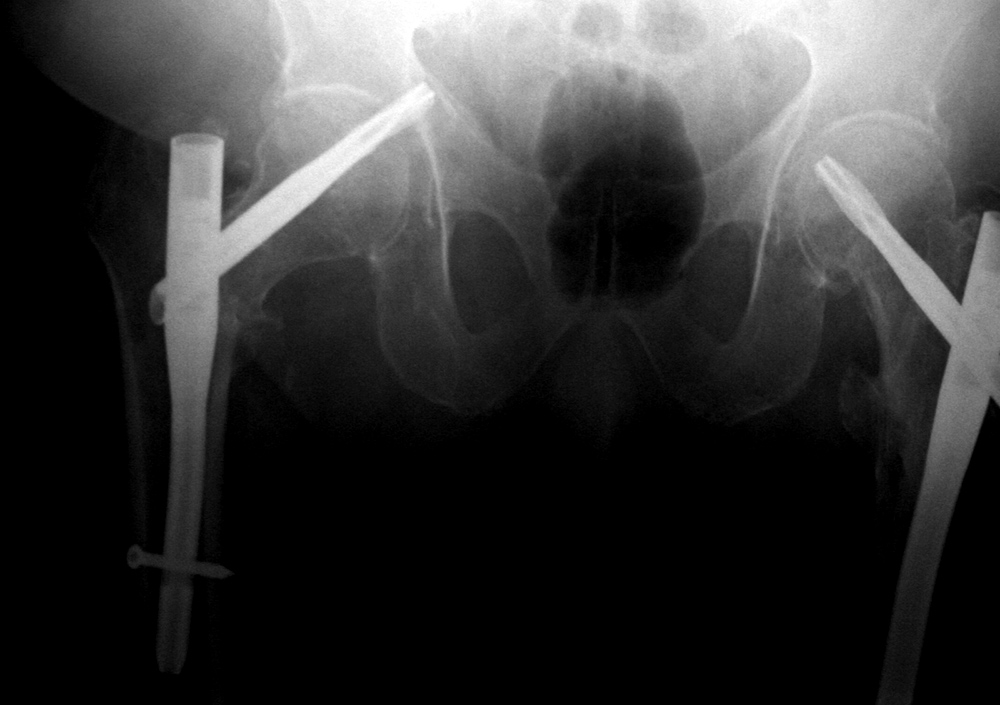

| 36 year-old man with bullet wound in 2003 complicated by femur fracture infected non-union treated by multiple attempts with external fixation and open reduction and internal fixation (ORIF). Radiography 12 years later shows chronic fracture hypertrophic nonunion, multiple shrapnel fragments, and breakage of a periarticular fixation plate. |